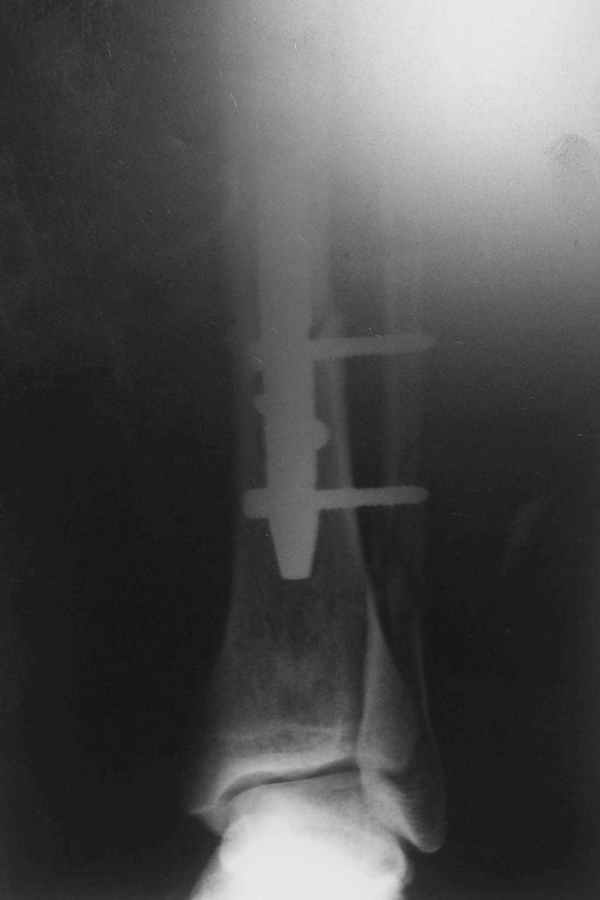

В 2002 г. была у нас больная с ложным суставом бедра и остеомиелитом (как оказалось), после удаления пластины. Гвоздь с блокированием.

Потекло через месяц - открылось 2 свища по старому рубцу от давно удаленной пластины. На фоне гноя раза три завинчивал обратно винты, которые вылезали латерально, прямо через свищ. Потом таки провел дополнительно винты мимо гвоздя, и убрал вверху статический винт. Острый гнойный процесс стих, свищи мыла она дома дважды в день водным хлоргексидином, ходила с возрастающей нагрузкой, а к 10 мес. и свищи закрылись, и срослось. Итоговые снимки от 18 апреля 2003 г. прилагаю.